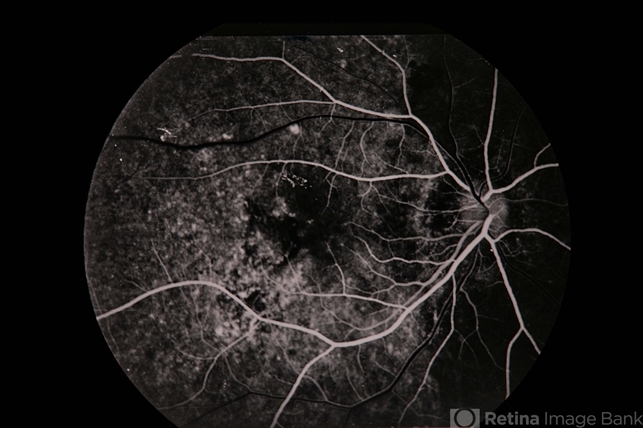

Pseudo-POHS / Lyme

PseudoPOHS Lyme

presumed ocular histoplasmosis syndrome (POHS), Lyme disease

Pseudo-POHS / lyme.